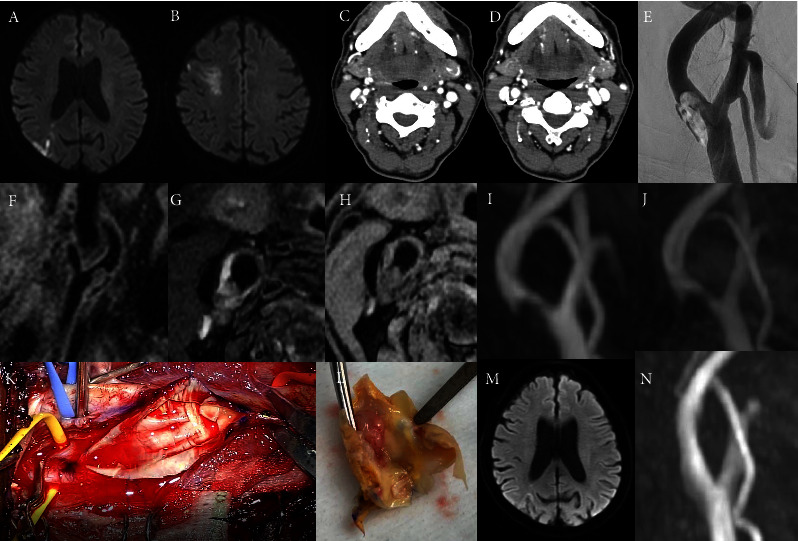

We report a patient with a symptomatic intraluminal internal carotid artery thrombus clinically revealed by cerebral infarction. In the preoperative evaluation, it was revealed that essential thrombocythemia existed in the background. Therefore, medical treatment with antithrombotic agents in conjunction with hydroxycarbamide for essential thrombocythemia was initiated, but the thrombus was not dissolved by three weeks. At this time, the patient underwent carotid endarterectomy, which removed the thrombus completely with its adjacent plaque without any perioperative stroke. The possibility of essential thrombocythemia may also be kept in mind when an increased platelet count is observed in patients with internal carotid artery thrombus. It is a reasonable option to precede medical treatment, including anticoagulant therapy, by setting the time limit for surgical intervention in such a disease state.